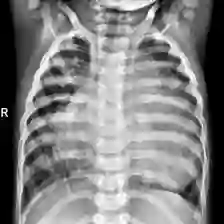

Coronavirus Disease 2019 (COVID-19) demonstrated the need for accurate and fast diagnosis methods for emergent viral diseases. Soon after the emergence of COVID-19, medical practitioners used X-ray and computed tomography (CT) images of patients' lungs to detect COVID-19. Machine learning methods are capable of improving the identification accuracy of COVID-19 in X-ray and CT images, delivering near real-time results, while alleviating the burden on medical practitioners. In this work, we demonstrate the efficacy of a support vector machine (SVM) classifier, trained with a combination of deep convolutional and handcrafted features extracted from X-ray chest scans. We use this combination of features to discriminate between healthy, common pneumonia, and COVID-19 patients. The performance of the combined feature approach is compared with a standard convolutional neural network (CNN) and the SVM trained with handcrafted features. We find that combining the features in our novel framework improves the performance of the classification task compared to the independent application of convolutional and handcrafted features. Specifically, we achieve an accuracy of 0.988 in the classification task with our combined approach compared to 0.963 and 0.983 accuracy for the handcrafted features with SVM and CNN respectively.

翻译:2019年科罗纳病毒疾病(COVID-19)表明需要准确和快速的诊断方法来治疗突发病毒疾病。在COVID-19出现后不久,医疗从业人员就使用X光和计算成的病人肺部透视图像来检测COVID-19。机器学习方法能够提高X光和CT图像中COVID-19的识别准确性,提供近实时结果,同时减轻医疗从业人员的负担。在这项工作中,我们展示了辅助矢量机(SVM)分类器(SVM)的功效,该分类机受过从X光胸部扫描中提取的深层脉冲和手动特征相结合的培训。我们使用这些特征组合来区分健康的、普通的肺炎和COVID-19病人。综合特征方法的性能与标准的脉冲神经神经网络(CNN)和受过手工制作特征培训的SVM相比。我们发现,将我们新框架的特征结合起来,与独立应用脉动和手动特征相比,可以提高分类工作的性能。具体地说,我们实现了0.983和0.983的精确度,与0.983和0.983的S手动方法相结合。